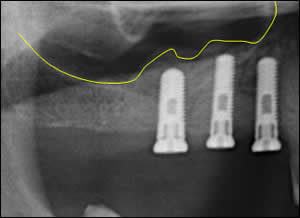

Fig 4: Tracing of the repositioned sinus floor providing ample space for 3 dental implants.